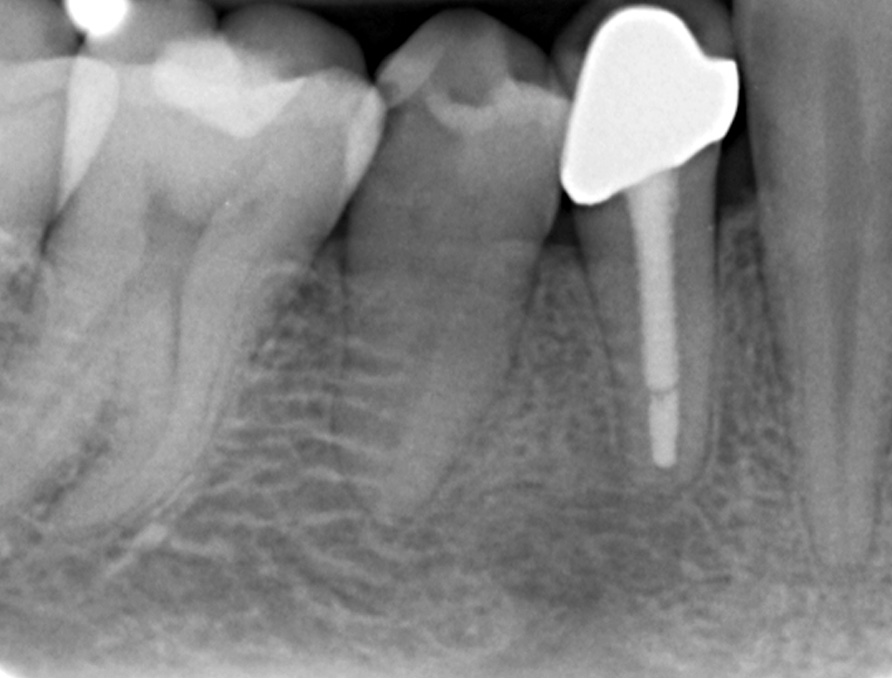

Röntgenologischer Ausgangsbefund

Röntgenologischer Ausgangsbefund im August 1996 bei Zahn 44 mit chronisch apikaler Parodontitis; Zustand vor umfangreicher ZE-Neuversorgung. Erste Therapie der Wahl ist in diesem Fall immer die konventionelle Wurzelkanalbehandlung ohne primär chirurgische Intervention

Wurzelfüllung

Wurzelfüllung im Januar 1997 in lateraler Kondensation mit normierter Guttapercha und AH 26. In der gleichen Sitzung wurde ein Titanstift adhäsiv inseriert mit dessen Hilfe der adhäsive Aufbau des Zahnes erfolgte